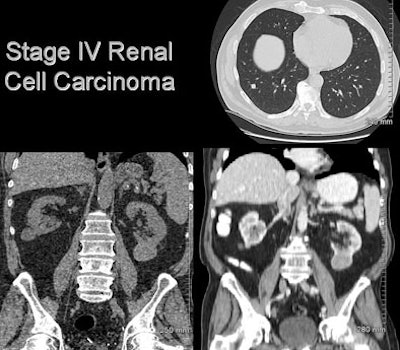

- Renal cell carcinoma (n = 4)

![]() |

| A man in his 70s underwent CT colonography screening; MDCT revealed a large renal mass. Workup also revealed multiple lung nodules. He was diagnosed with metastatic renal cell carcinoma; however, no intervention has been performed due to multiple comorbidities, and the patient has done well. |